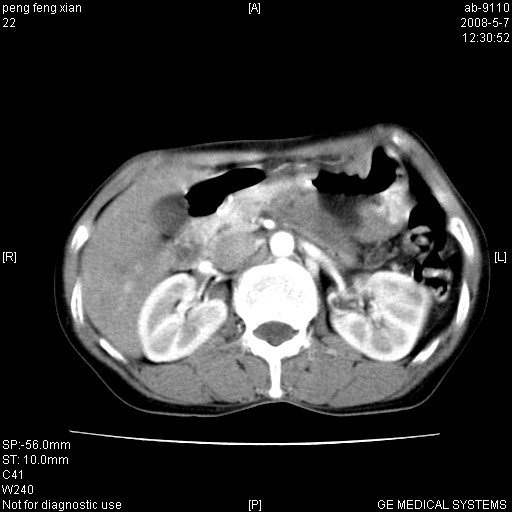

女,56岁。b超左一腹包块,考虑胃肠道肿瘤。

胃体部胃壁增厚,不均匀性强化,与胰腺分解欠情.

考虑:胃癌,胰腺受侵待除外.

典型胃癌胰体尾部受侵。

胃癌并转移。